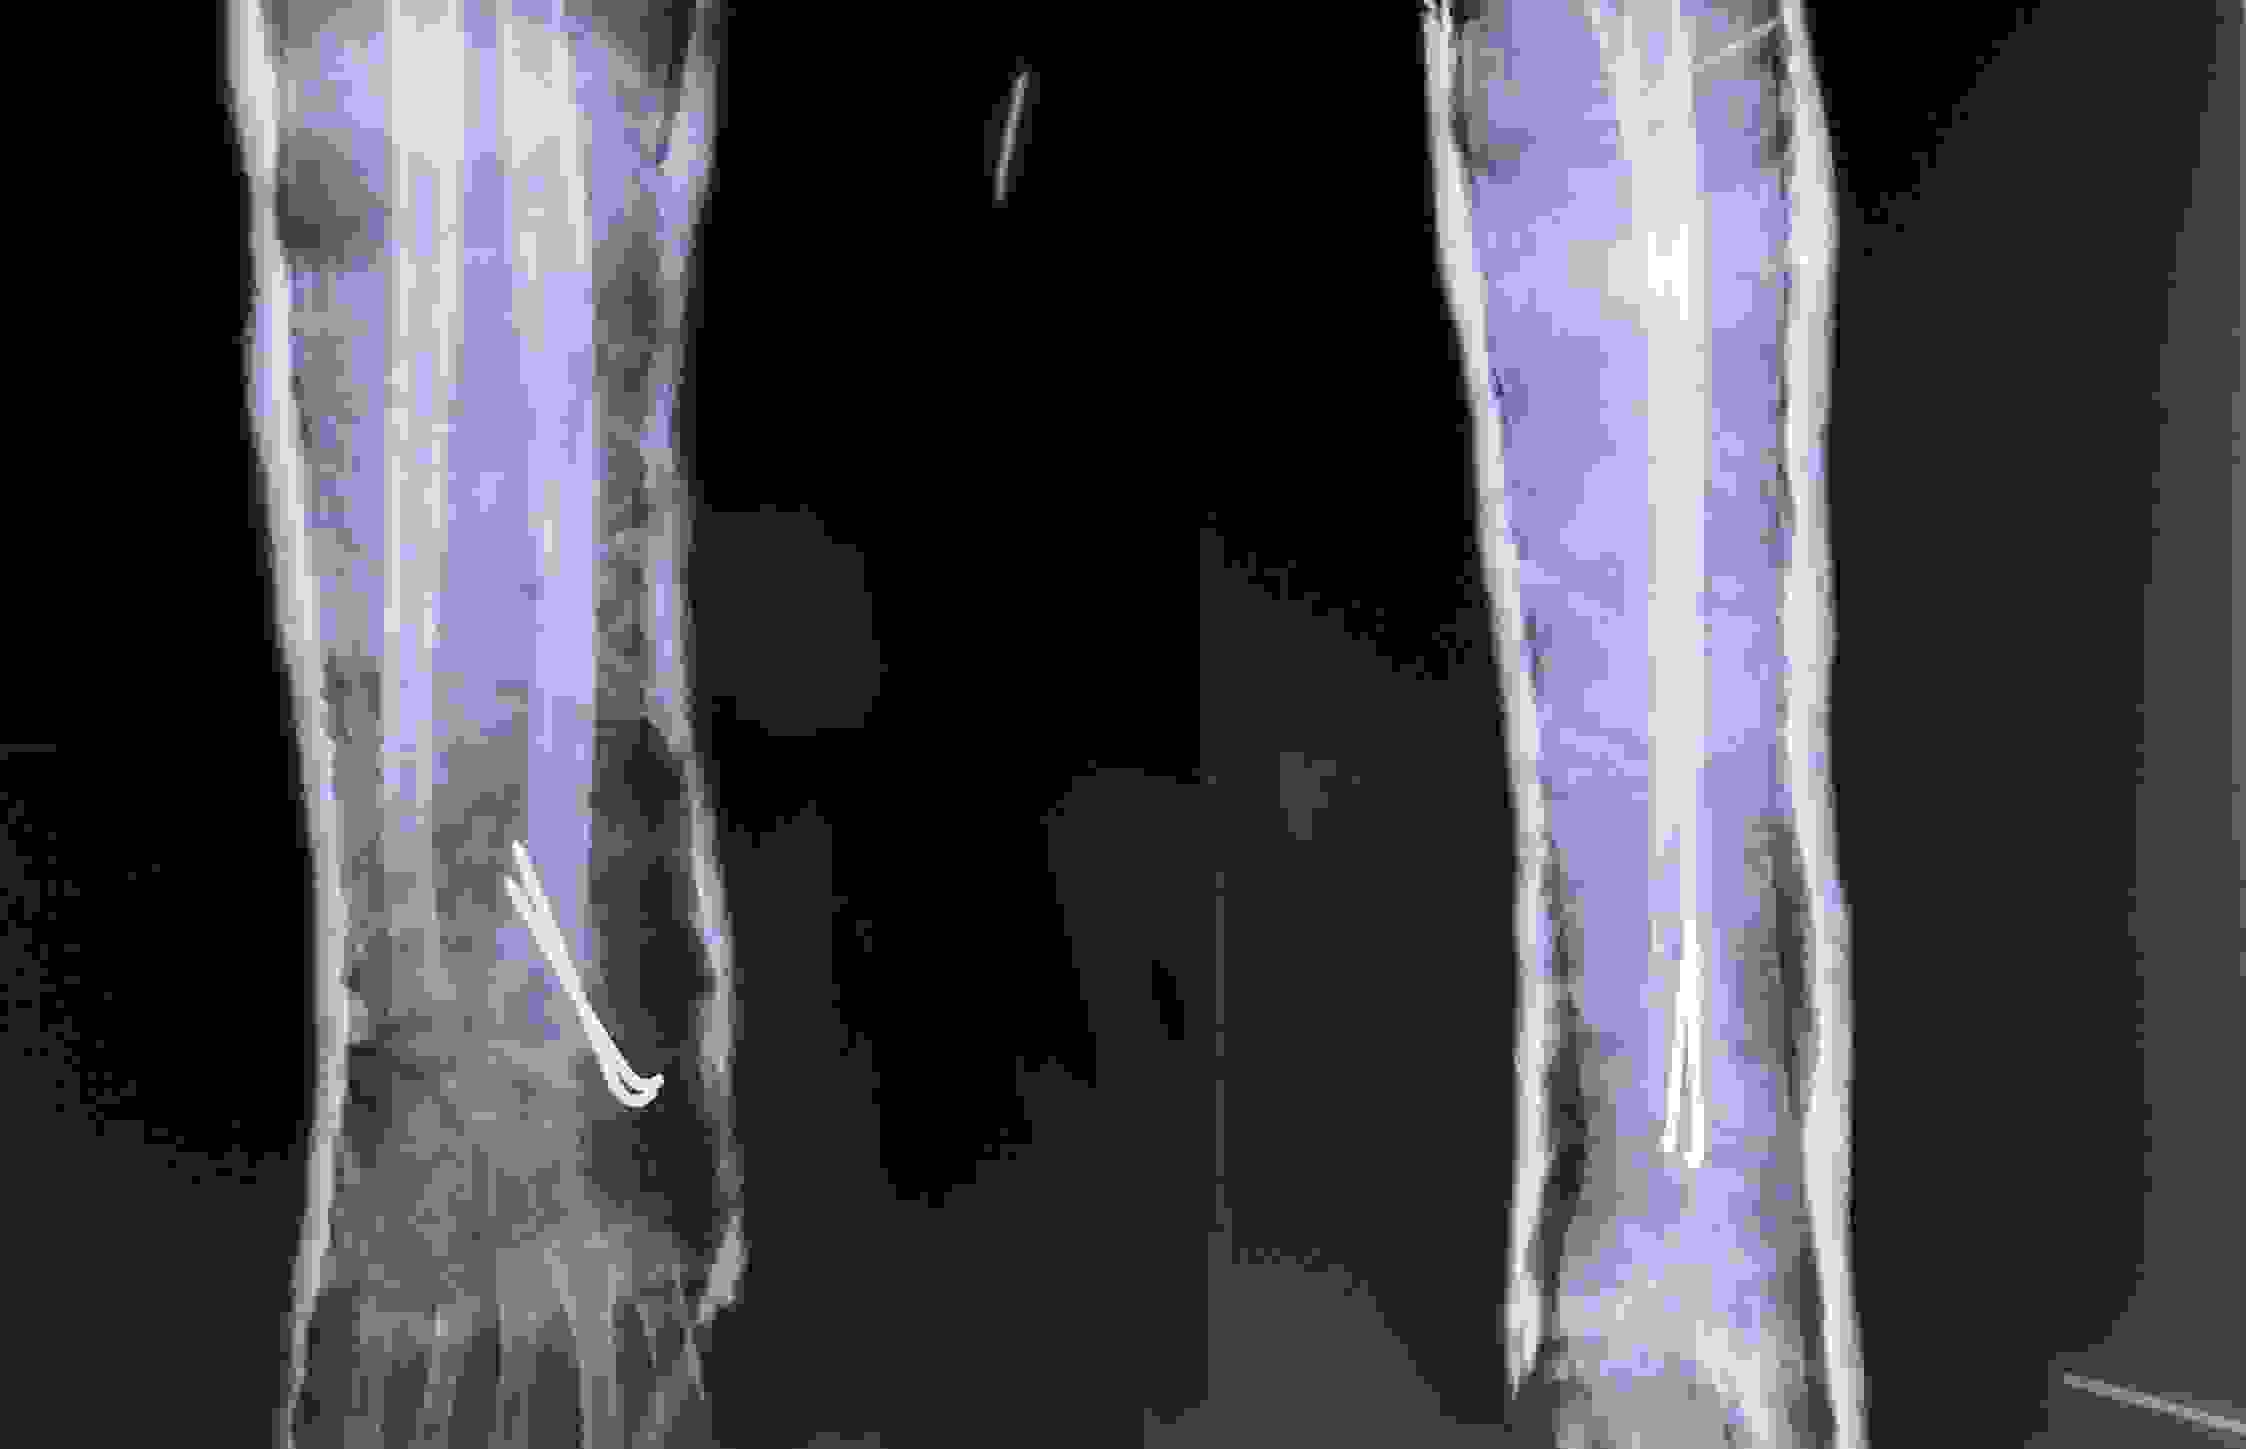

Bệnh viện Chấn thương Chỉnh hình Nghệ An “cứu sống” bàn tay đứt lìa cho bệnh nhân 67 tuổi

Đứt rời một phần chi thể không chỉ là tổn thương nghiêm trọng về mặt chức năng mà còn ảnh hưởng lớn đến thẩm mỹ nếu không được xử lý chính xác và kịp thời. Với sự phát triển của kỹ thuật vi phẫu, mỗi năm Bệnh viện Chấn thương chỉnh hình Nghệ An “cứu sống” hàng trăm bệnh nhân bị đứt rời chi hoặc đứt mạch máu, dây thần kinh quan trọng…